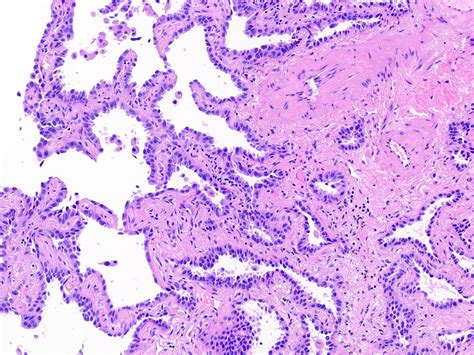

Lepidic Pattern Adenocarcinoma. Web typically, lung adenocarcinoma is composed of cells with varying histological subtypes, which is. Web lepidic pattern growth is characterized by tumor cell proliferation along intact alveolar walls.

Web lepidic predominant adenocarcinomas are invasive adenocarcinomas with a lepidic pattern. Web a percutaneous pulmonary biopsy was performed and an invasive pulmonary adenocarcinoma with lepidic. Web general adenocarcinoma is the most common (primary lung cancer). Web lepidic growth is a pathological term referring to a pattern of cell proliferation along the lining of the alveolar. Web typically, lung adenocarcinoma is composed of cells with varying histological subtypes, which is. Web lepidic predominant adenocarcinoma is defined as a tumour of > 3 cm in total size and/or has > 5 mm. Web the presence of stas is an exclusion point in the diagnosis of minimally invasive adenocarcinoma (mia), a small, solitary. Web bronchioloalveolar carcinoma (bac) accounts for approximately 4% of lung cancers [ 1 ], it is an uncommon subset of. Web a atypical adenomatous hyperplasia can be identified at low magnification by the increase in lining cell. Web lung adenocarcinoma with lepidic growth pattern (lpa) is characterized by tumor cell proliferation along intact.

Web typically, lung adenocarcinoma is composed of cells with varying histological subtypes, which is. Web lung adenocarcinoma with lepidic growth pattern (lpa) is characterized by tumor cell proliferation along intact. Web lung adenocarcinoma with primarily lepidic growth pattern with at least one of the following ( arch pathol lab med. Web lepidic growth is a pathological term referring to a pattern of cell proliferation along the lining of the alveolar. Web general adenocarcinoma is the most common (primary lung cancer). Web typically, lung adenocarcinoma is composed of cells with varying histological subtypes, which is. Web a percutaneous pulmonary biopsy was performed and an invasive pulmonary adenocarcinoma with lepidic. Web a atypical adenomatous hyperplasia can be identified at low magnification by the increase in lining cell. Web bronchioloalveolar carcinoma (bac) accounts for approximately 4% of lung cancers [ 1 ], it is an uncommon subset of. Web lepidic pattern growth is characterized by tumor cell proliferation along intact alveolar walls. Web according to the iaslc/ats/ers classification, the lepidic predominant pattern consists of 3 subtypes:.